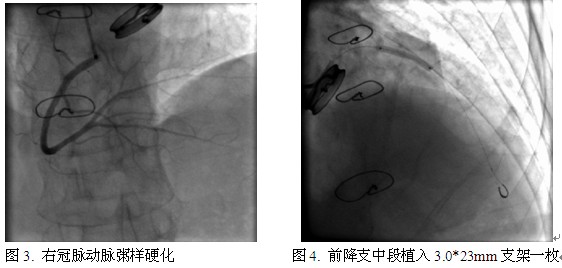

入院后立即给予拜阿司匹林、氯吡格雷抗血小板(负荷量)以及调脂、降压、扩管等对症治疗后,送往心导管室。经桡动脉途径行冠脉造影。检查提示:左主干未见明显狭窄,前降支中段狭窄90%,回旋支中段狭窄40%,右冠脉动脉粥样硬化(图1~3)。造影结束,送EBU3.5/GC至左冠脉口,将BWM指引导丝送至前降支远端,于前降支中段置入3.0*23mm药物洗脱支架一枚。重复造影:支架贴壁良好,未见明显残余狭窄,血流TIMI 3级(图4~5)。术中共使用肝素3500u。术后患者恢复良好,拜阿司匹林+氯吡格雷+华法林三联抗栓治疗6个月,之后拜阿司匹林+华法林维持到术后12个月,最后终身口服华法林治疗。